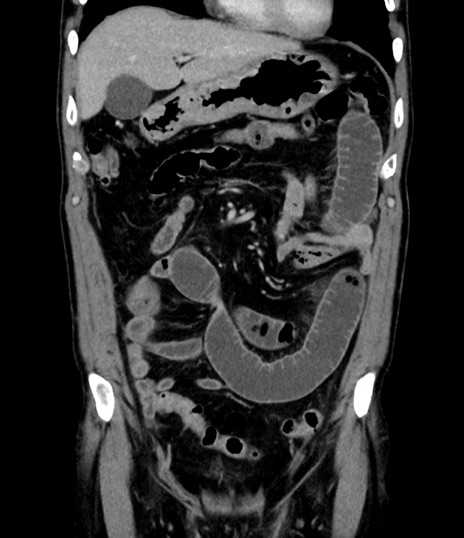

症例8(冠状断像)

【症例】 60歳代男性

【主訴】 黒色吐物

【現病歴】 4日前から嘔気自覚、2日前の朝食後にも嘔気あり、自分で手で嘔吐反射起こし嘔吐したところ血が混ざっていたため受診。

【既往歴】 5年前汎発性腹膜炎を伴う急性虫垂炎で手術、高血圧、前立腺肥大症、高脂血症

【身体所見】 腹部正中に手術癩痕あり 腹部平坦・軟圧痛なし膨満感あり

【データ】WBC 8400、CRP 4.54